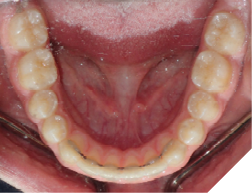

The majority of the orthodontic practices offer a period of “supervised retention” to their patients and communicates the customized retention recommendation with the patient’s general dentists. It is extremely important to work as a team to achieve long term clinical success in maintaining a functional bite and aesthetic smile. The general dentists continue to see their patients on a regular basis and have an opportunity to assess the orthodontic retainers and the bite after the supervised retention period is completed by the orthodontists. With great care, orthodontic retainers would serve for a long time (Fig. 1) without any major issues. However, in some cases, the failure to notice the clinical problems early on results in functional issues that would require a comprehensive orthodontic treatment to correct it (Fig. 2).

Fig. 1A

Fig. 1B

Fig. 1C